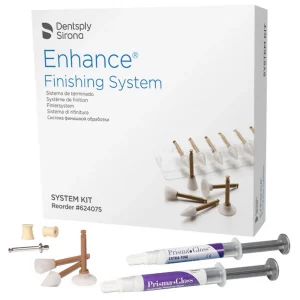

- Efficiency: Designed for efficient and effective restorations, the kit includes all necessary components, such as shade guides, sculpting instruments, and finishing materials, streamlining the restoration process for dental professionals.